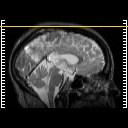

SPECT TC Study #2 -- Slice #50

[Home][Help][Clinical][Tour 1][Tour 2][Tour 3] Slice 50

Click on sagittal image to select slice. Click on thin tickmark to change timepoint, or thick tickmark for overlay.